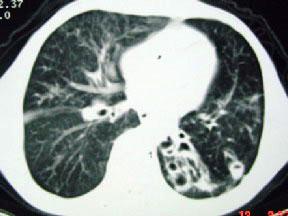

男,12岁,反复咳嗽咳痰多年,CT如图3,最可能的诊断为 ( )A.先天性支气管囊肿B.肺结核C.肺发育不全D.肺隔离症E.肺脓肿

问题 男,12岁,反复咳嗽咳痰多年,CT如图3,最可能的诊断为 ( )

选项 A.先天性支气管囊肿 B.肺结核 C.肺发育不全 D.肺隔离症 E.肺脓肿

答案 A